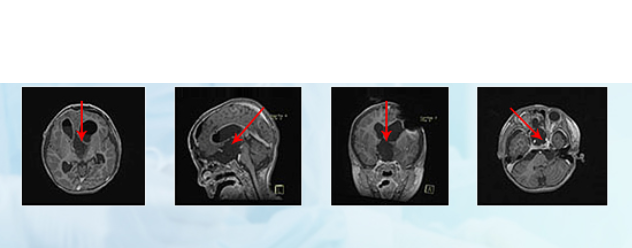

術(shù)前MR

國(guó)內(nèi)一次手術(shù)后:

德國(guó)巴教授INI手術(shù)結(jié)果:

更新診斷“視神經(jīng)膠質(zhì)瘤”,

腫瘤全切,未殘留長(zhǎng)期神經(jīng)功能障礙,

術(shù)后兩周出院,視力明顯好轉(zhuǎn),

可自行站立、短距離行走。

手術(shù)過(guò)程記錄:通過(guò)額骨顱骨開顱術(shù)和大腦半球間穹窿入路腫瘤切除術(shù)直至Monro孔(室間孔),并沿著腦室壁向中腦行進(jìn)。右側(cè)視神經(jīng)被腫瘤浸潤(rùn)包裹,但是左側(cè)視神經(jīng)被小心地從腫瘤腫塊中剝離出來(lái),垂體腺和垂體柄也被小心的保護(hù)起來(lái)。沒(méi)有術(shù)中并發(fā)癥。

術(shù)后病理結(jié)果:小冬患的是毛細(xì)胞型星形細(xì)胞瘤,WHO I級(jí),是一種低級(jí)別膠質(zhì)瘤。根據(jù)美國(guó)腦膠質(zhì)瘤NCCN治療指南及臨床數(shù)據(jù)統(tǒng)計(jì)提示,術(shù)后不需要進(jìn)行放化療等治療(放化療對(duì)病情控制無(wú)益,但是對(duì)身體的傷害大于獲益),而且20年總體生存率87%±0.8%。

術(shù)后1年,小冬一家來(lái)到INC面對(duì)面咨詢“巴教授”,原本已經(jīng)失明的小冬現(xiàn)在視力漸漸恢復(fù)了,復(fù)查后MRI影像也顯示腫瘤并無(wú)增長(zhǎng),小朋友恢復(fù)了以往的活潑可愛(ài)。